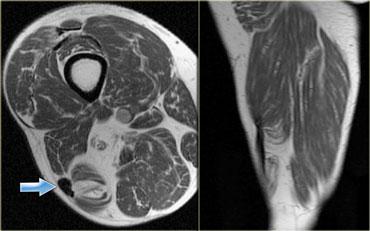

Ở hình bên trái của một bệnh nhân bị chấn thương đầu dài của cơ nhị đầu đùi.

Có những thay đổi mãn tính điển hình như dày gân khu trú (mũi tên xanh) và teo cơ nặng.